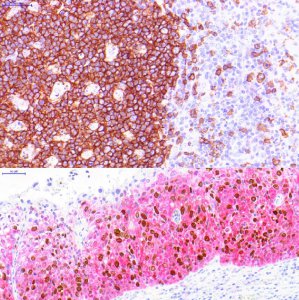

Hisztokémiai és immunhisztokémiai reagensek fejlesztése, gyártása, forgalmazása

- hisztokémiai és immunhisztokémiai reagensek fejlesztése, gyártása, forgalmazása